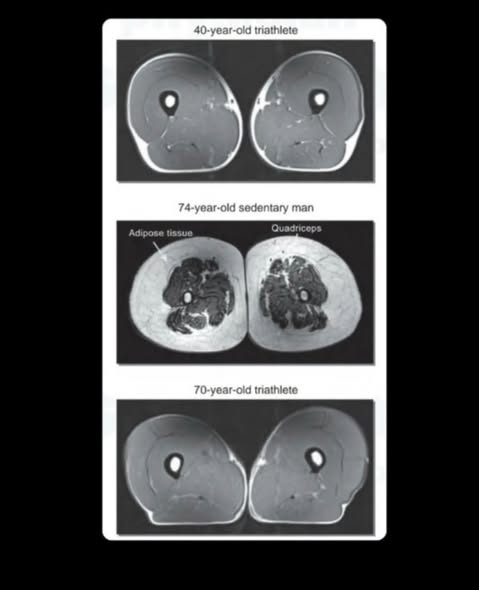

Bilde 1 viser MR bilder av 3 ulike personer:

Øverst: 40 år gammel triatlet.

I midten: 74 år gammel person med stillesittende livsstil.

Nederst: 70 år gammel triatlet.

Det mørke området viser muskel, og det lyse området viser fett.